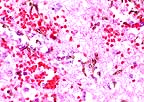

Focal necrohemorrhagic encephalitis in a meerkat with phaeohyphomycosis (13K)

Pigmented fungal hyphae of Cladosporium sp. in the cerebrum of a meerkat (Suricata suricatta). (HE, 400X, 59K)

Gross Pathology: Gross lesions were restricted to the central nervous system. The dorsomedial aspect of the left cerebral hemisphere contained a firm, well-vascularized brown and white mottled nodular mass measuring 1.5 cm in greatest diameter. This lesion involved the corpus callosum but did not extend into the right cerebral hemisphere.

Impression cytology of the brain lesion revealed high numbers of RBC's, neutrophils, and macrophages with occasional lymphocytes. Numerous brown septate branching fungal hyphae were also present.

AFIP Diagnosis: Cerebrum: Encephalitis, necrohemorrhagic, acute, focally extensive, severe, with necrotizing vasculitis and pigmented fungal hyphae, meerkat (Suricata suricatta), viverrid.

Conference Note: Phaeohyphomycosis usually causes subcutaneous mycosis in mammals. In tissue, the fungal hyphae are pigmented, septate, and have walls that are irregular in width and length and demonstrate non-dichotomous branching. Systemic infections seldom arise from subcutaneous lesions; they are usually acquired via the respiratory tract. Animals that develop systemic phaeohyphomycosis are often immunocompromised or debilitated.